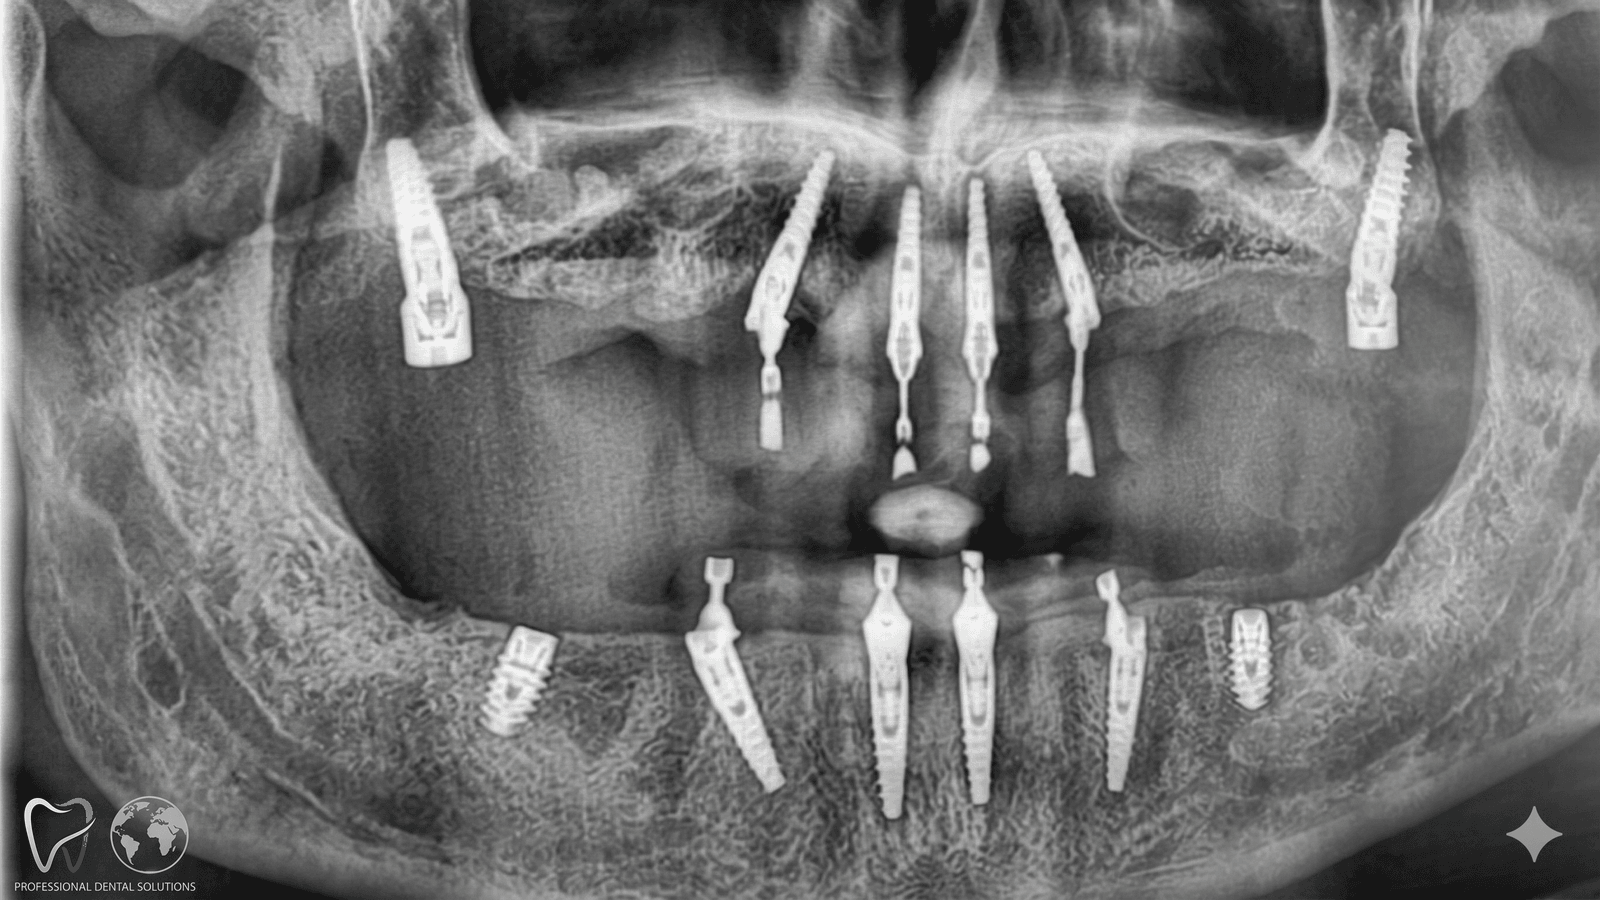

Avevo perso quasi tutti i denti dell'arcata superiore e in Italia mi avevano chiesto 24.000€ per un All-on-6. A Tirana ho fatto lo stesso lavoro a 9.500€, con impianti Nobel Biocare e protesi definitiva in zirconia. Il dentista ha studiato in Germania, parlava italiano, era preparatissimo. Sono passato in due viaggi di 4 giorni e ora mangio di nuovo come prima.

Stefano V.

Padova • Impianti All-on-6